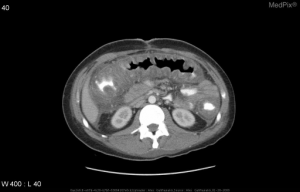

Pseudomembranous colitis from C. difficile on abdominal CT demonstratin diffuse colonic wall thickening and a shaggy endoluminal contour.